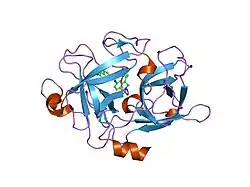

Urokinase is a 411-residue protein, consisting of three domains: the serine protease domain (consisting of residues 159–411), the kringle domain (consisting of residues 50-131), and the EGF-like domain (consisting of residues 1-49). The kringle domain and the serine protease domain are connected by an interdomain linker or connecting peptide (consisting of residues 132–158). Urokinase is synthesized as a zymogen form (prourokinase or single-chain urokinase), and is activated by proteolytic cleavage between Lys158 and Ile159. The two resulting chains are kept together by a disulfide bond between Cys148 and Cys279.[9]